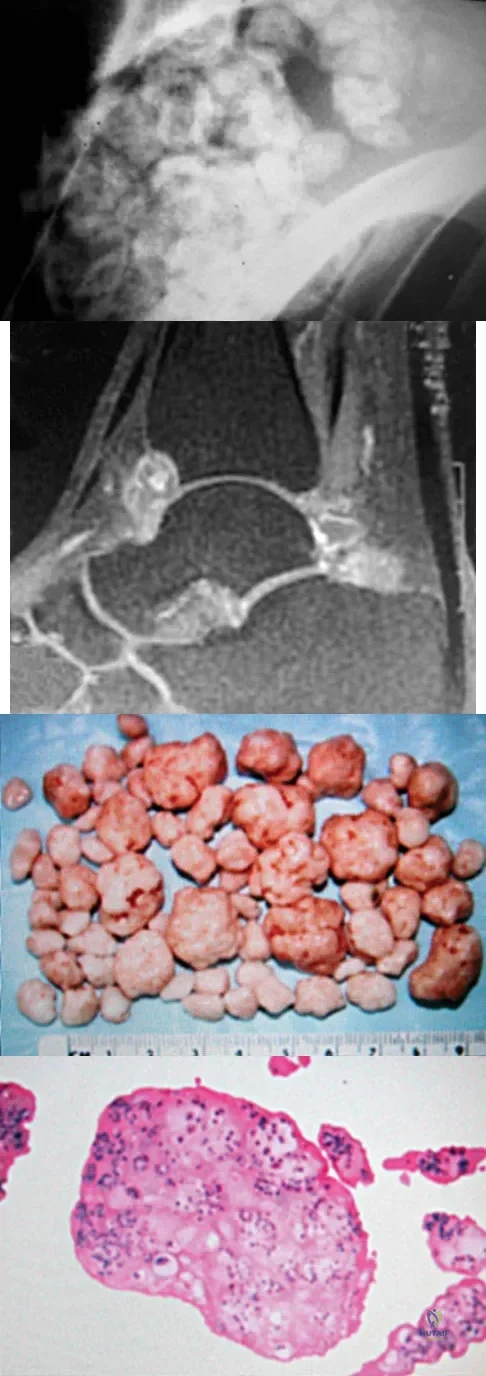

A 19-year-old girl has had pain and swelling in the right ankle for the past 4 months. She denies any history of trauma. Examination reveals a small soft-tissue mass over the anterior aspect of the ankle and slight pain with range of motion of the ankle joint. The examination is otherwise unremarkable. A radiograph and MRI scan are shown in Figures 45a and 45b, and biopsy specimens are shown in Figures 45c and 45d. What is the most likely diagnosis?

Explanation